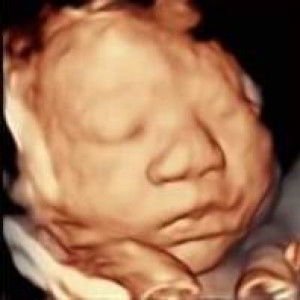

Hello mga mi , 36 weeks na po ako ng pa ie ako knina 4cm na pero wlang pain ???

4cm na pero wlang pain